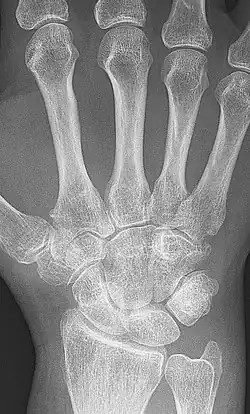

X-rays of the hands and feet are generally performed when many joints affected. In RA, there may be no changes in the early stages of the disease or the x-ray may show osteopenia near the joint, soft tissue swelling, and a smaller than normal joint space. As the disease advances, there may be bony erosions and subluxation. Other medical imaging techniques such as magnetic resonance imaging (MRI) and ultrasound are also used in RA.[23][56]

X-ray of the hand in rheumatoid arthritis. -

Closeup of bone erosions in rheumatoid arthritis.[58]